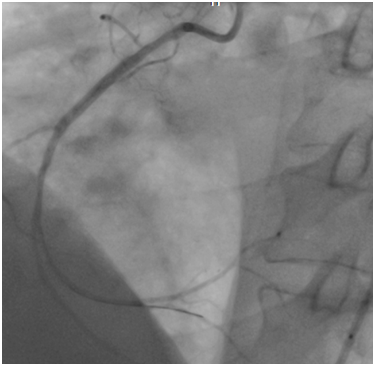

The first case

A 53year-old male without cardiovascular risk factor was admitted to our hospital in 2005 due to an inferior AMI. The culprit lesion was thrombotic occlusion of proximal right coronary artery (RCA). Primary percutaneous coronary intervention to RCA with a BMS (3.00x24mm; Liberté®; Boston scientific, Natick, Massachusetts) was done with an excellent result. No post-dilatation was needed. Dual antiplatet therapy was prescribed for one month (Clopidogrel 75mg once a day). Then; aspirin (ASA) was prescript alone for life. Eight years later, he suffered from a severe chest pain relevant to a recurrent inferior AMI. Hence, he was immediately referred for a primary angioplasty. In-stent huge thrombosis was located in the proximal edge of the stent of the RCA. IC stent® (Siemens Healthcare GmbHErlangen, Germany) had showed an underdeployment of the stent. Then, a predilatation with a non compliant Balloon had restored a TIMI III flow. He was discharged five days later with a daily 75mg of clopidogrel for 12months and 100mg of ASA associated daily for life (Figure 1-3).

Figure 1 Thrombotic occlusion at the proximal edge of the bare metal stent.